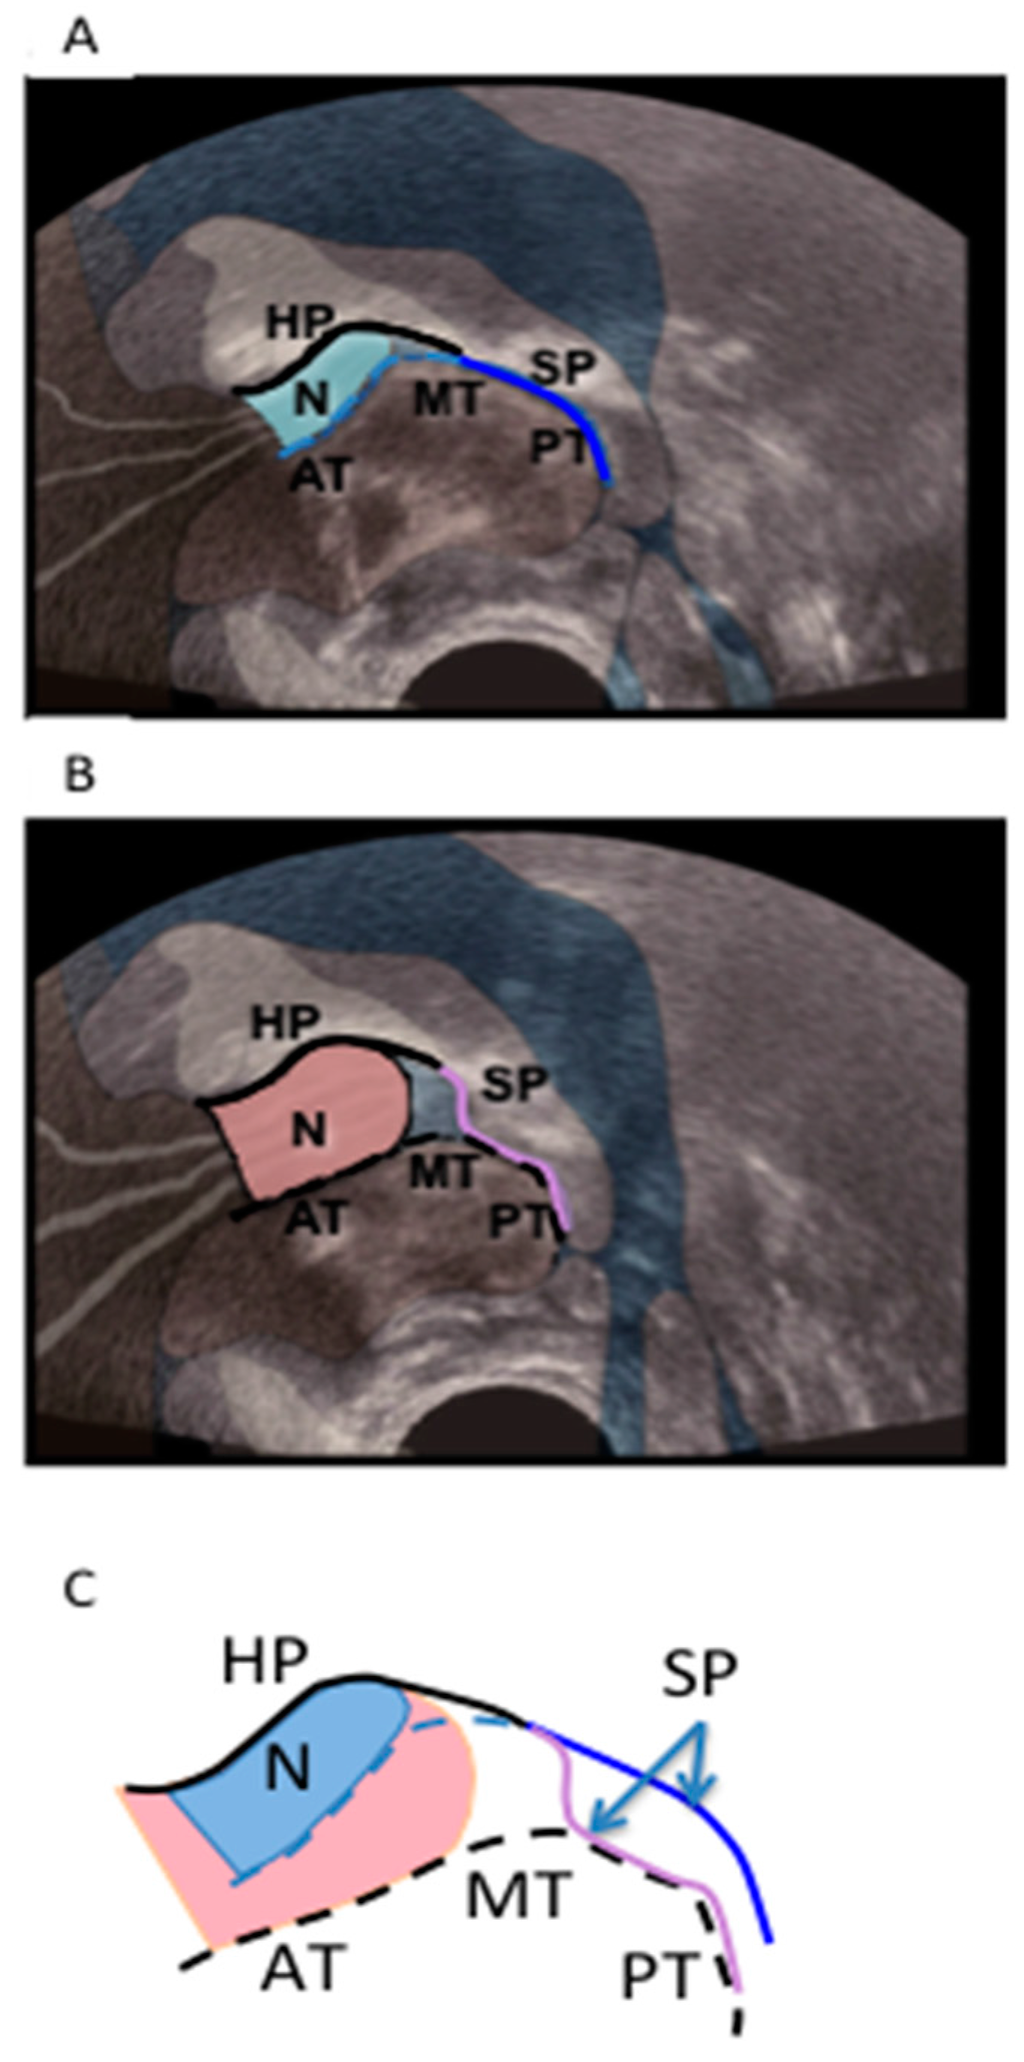

For each infant, the first recorded cine clip of optimal imaging during nutritive sucking that included at least three full suck cycles was isolated from Chart v4.5 (ADInstruments, Castle Hill, NSW, Australia) and stored on a MacBook Pro (Max OSX, V 10.5.7). For each infant, two images were then selected from each of three suck cycles: one when the mid-tongue was raised to its most superior level (tongue up, Figure 1A), and the second when the mid-tongue was lowered to its most inferior level (tongue down, Figure 1B). The following measurements were made on each selected image using Screen Calipers, V. 3.2 (Iconico Inc, New York, NY, USA) as previously described [12]: the depth of the space between the HSPJ and the mid-tongue (intra-oral space depth); the N-HSPJ distance; and nipple diameters at 2, 5, 10 and 15 mm from the nipple tip (location).

Figure 1. Submental ultrasound image of nipple in infant’s mouth during breastfeeding at, (A) the tongue up position, and (B) the tongue down position. (C) is a diagrammatic representation of the nipple shape and tongue position at tongue up (blue) and tongue down (pink); HP, hard palate; SP, soft palate; N, nipple; AT, anterior tongue; MT, mid-tongue; PT, posterior tongue.